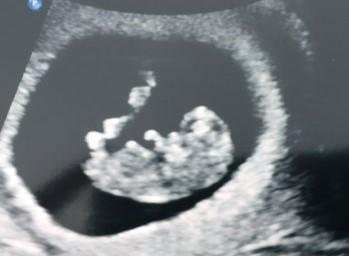

8 седмица